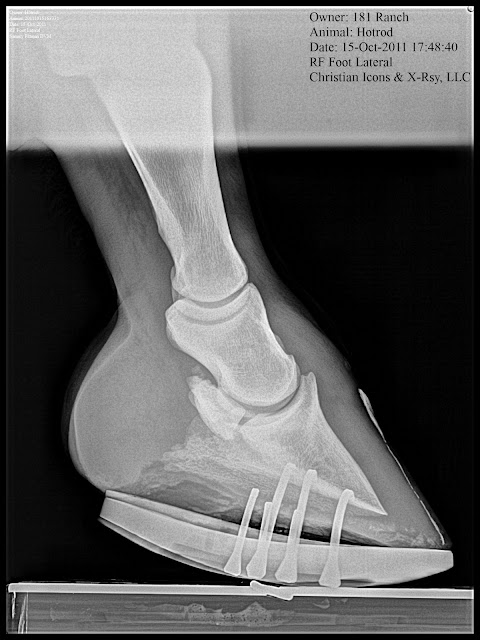

Below: Quarter race horse that goes off after 150 yards or so and quits running. 4yrs old and has moderate navicular changes already. Placed in Rockered Race shoe from NANRIC to increase TSA and PA. This will unload DDF/nav bone engagement and small osteophyte at dorsal aspect of coffing joint.